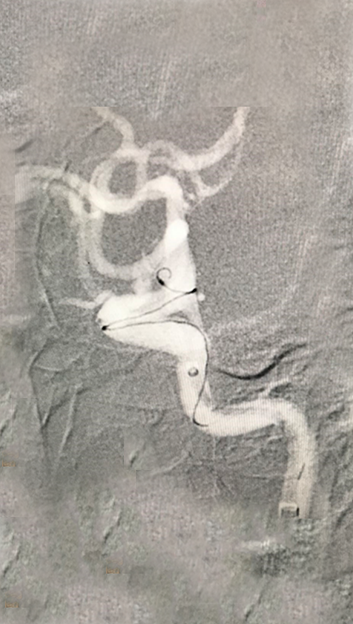

填入5个超软圈,美敦力Prime系列对瘤壁压力非常低,对脆弱的血泡样动脉瘤安全有保障;弹簧圈圈体非常柔软,有利于致密栓塞,阻隔血流。

APB 3-8-3D、APB 2-4-3D 、APB 2-4-2D,APB 2-3-2D,APB 1-1-2D

4.1)

造影显示动脉瘤致密栓塞

随访影像

术后一月复查的影像,动脉瘤未见复发及残留,载瘤动脉修复满意。